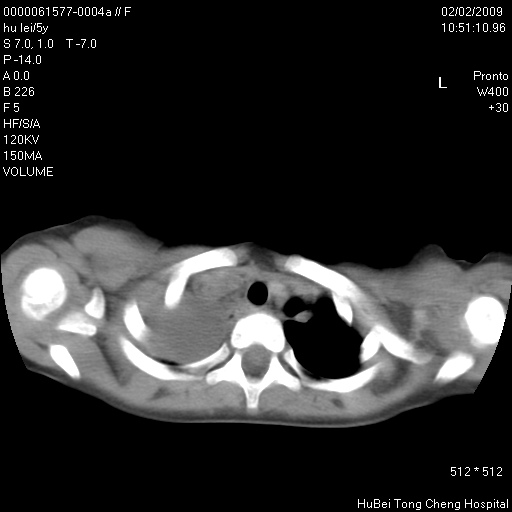

标题: PED1732:M5Y,右肺囊性占位!

患者:男,5。无明显不适,拍胸片考虑右肺囊肿。

行ct扫描,图象如下:

病灶与前胸壁和右上纵隔、叶间裂界限不清,病灶前缘及内侧缘看不到正常的肺组织,不能排除包裹性积液。